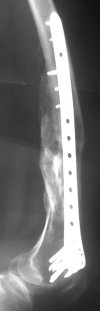

A new toy is more interesting and fashionable. And anyway it is not panacea, i have already seen presentations with LISS failures like the attached one presented by D.Seligson. And people also demonstrated incisions say that the method is not so LESS invasive as it supposed to be.